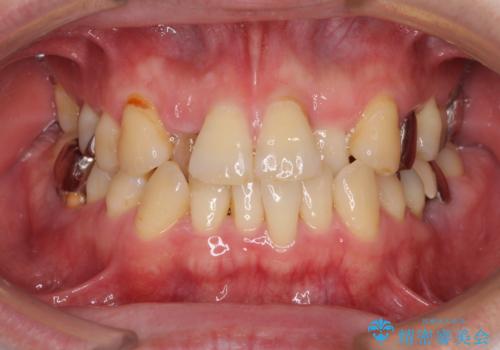

- 奥歯の痛みと前歯のデコボコを気にして来院された患者様です。

左右下顎の大臼歯は、ともに歯根が破折しており、抜歯が必要な状態でした。

咬み合わせは受け口傾向であり、上顎前歯の叢生が顕著であったことから、第1小臼歯抜歯による矯正治療も検討しましたが、下顎大臼歯を左右ともに抜歯するため、非抜歯による矯正治療を行うこととしました。